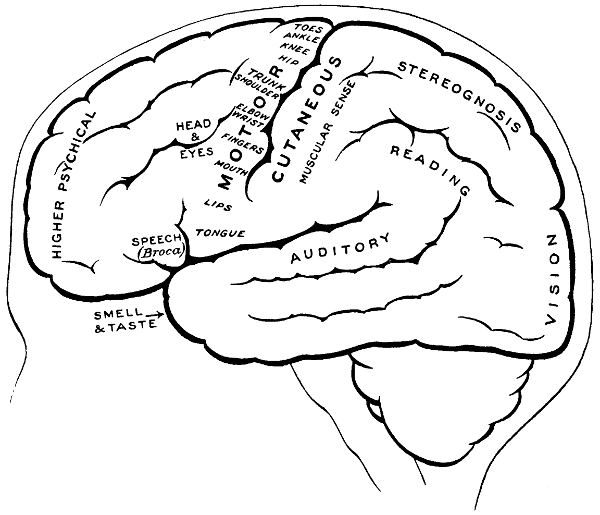

Fig. 3. The Cortical Motor and Sensory Areas.

The researches of Sherrington and Grünbaum,[2] Campbell,[3] and others tend to show that the cortical motor areas are situated entirely anterior to the central fissure or fissure of Rolando, extending above well over on to the mesial aspect of the brain, though not so far as the calloso-marginal fissure, and in the downward direction to within a short distance of the fissure of Sylvius. In the posterior direction the motor area includes the anterior boundary and part of the bottom of the fissure of Rolando, whilst in front it spreads, by means of gyri annectantes, on to that part of the brain which lies anterior to the precentral sulcus. The anterior termination is indefinite, but the motor strip is, on an average, not more than 3⁄4 inch in breadth.

The genua of the Rolandic fissure are said to bear a more or less definite relation to the motor areas. In my experience, however, they are too variable, and any importance which might obtain is further diminished by the fact that the surgeon should never rest content with that limited exposure of the brain which was so much in vogue till recent years. The suspected region is widely exposed by osteoplastic flap, and if doubt exists as to the particular part of cortex exposed the question is accurately settled by faradization.

[8]

This motor strip corresponds, from above downwards, to the movements of the contralateral lower extremity (toe to hip), trunk, upper extremity (shoulder to fingers), neck and face. It is a point of some general utility to bear in mind that the temporal crest intervenes approximately between the regions responsible for the movements of the upper extremity (above the crest) and those for the movements of the head and face (below the crest).

On the left side of the head—in normal right-handed individuals—the motor speech area of Broca corresponds to the third left frontal convolution, in the angle between the anterior and posterior horizontal limbs of the Sylvian fissure.

The ‘primary registration’ of ‘common sensation’ occurs in the post-central gyrus, immediately posterior to the fissure of Rolando. This tactile area occupies a position behind the fissure of Rolando[9] similar in extent to that occupied by the motor area in front. It commences at the bottom of the fissure of Rolando and extends backwards over rather more than half the exposed area of the post-central convolution. It reaches down to near the Sylvian fissure and extends over on to the mesial aspect of the brain. Furthermore, it is probable that sensation in any given part lies on more or less the same level as the corresponding motor area.

Immediately posterior to the tactile area and occupying the posterior and upper part of the post-central convolution, the area responsible for muscle-sense is situated.

Stereognosis—memory pictures, object perception, &c.—is referred to the superior parietal lobe.

Primary visual impressions are received in the occipital lobe, more especially on the mesial aspect thereof.

Finally, the four areas concerned in speech—motor speech, writing, reading, and hearing—are anatomically separated from one another and yet closely associated, so much so that one can hardly be involved without the other. The motor speech centre of Broca has already been mentioned as occupying—in right-handed individuals—the posterior part of the third left frontal convolution. Writing lies immediately above and in front, in the posterior part of the middle frontal gyrus, auditory impressions are received in the posterior and upper part of the first temporo-sphenoidal lobe, whilst the power of reading is dependent on the integrity of the supramarginal and angular gyri (see also Fig. 57).

Smell and Taste lie in close relation to the anterior pole of the temporo-sphenoidal lobes.